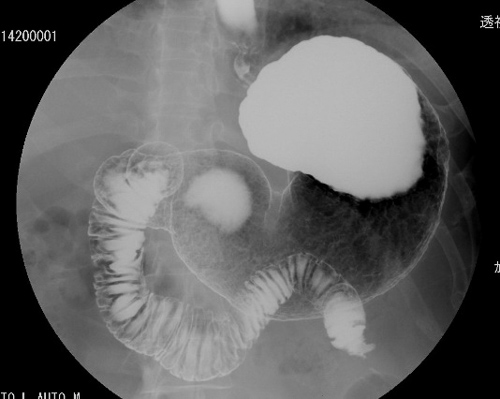

【透視検査】

X線を連続で出し、その画像を動画として観察できる装置です。造影剤を用いて胃腸などの動きを観察しながら撮影することができます。

内視鏡検査やチューブの挿入等の検査を進める際にも使用しています。